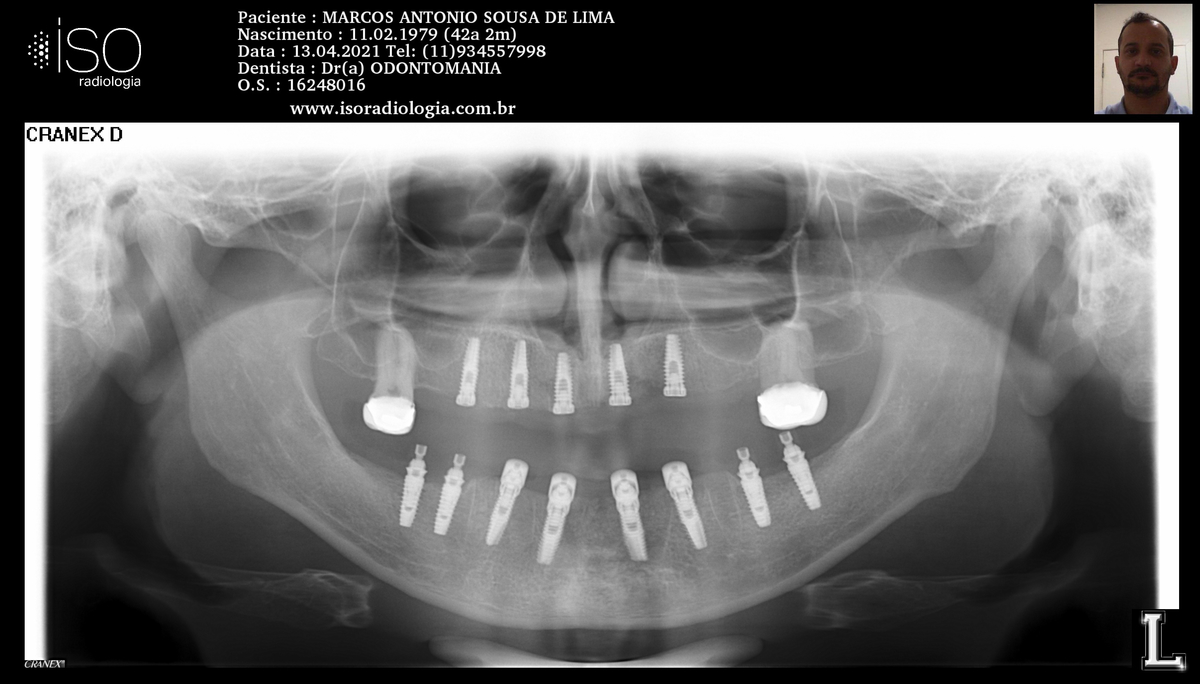

PRÓTESE TOTAL FIXA EM IMPLANTES

M.A.S.L.